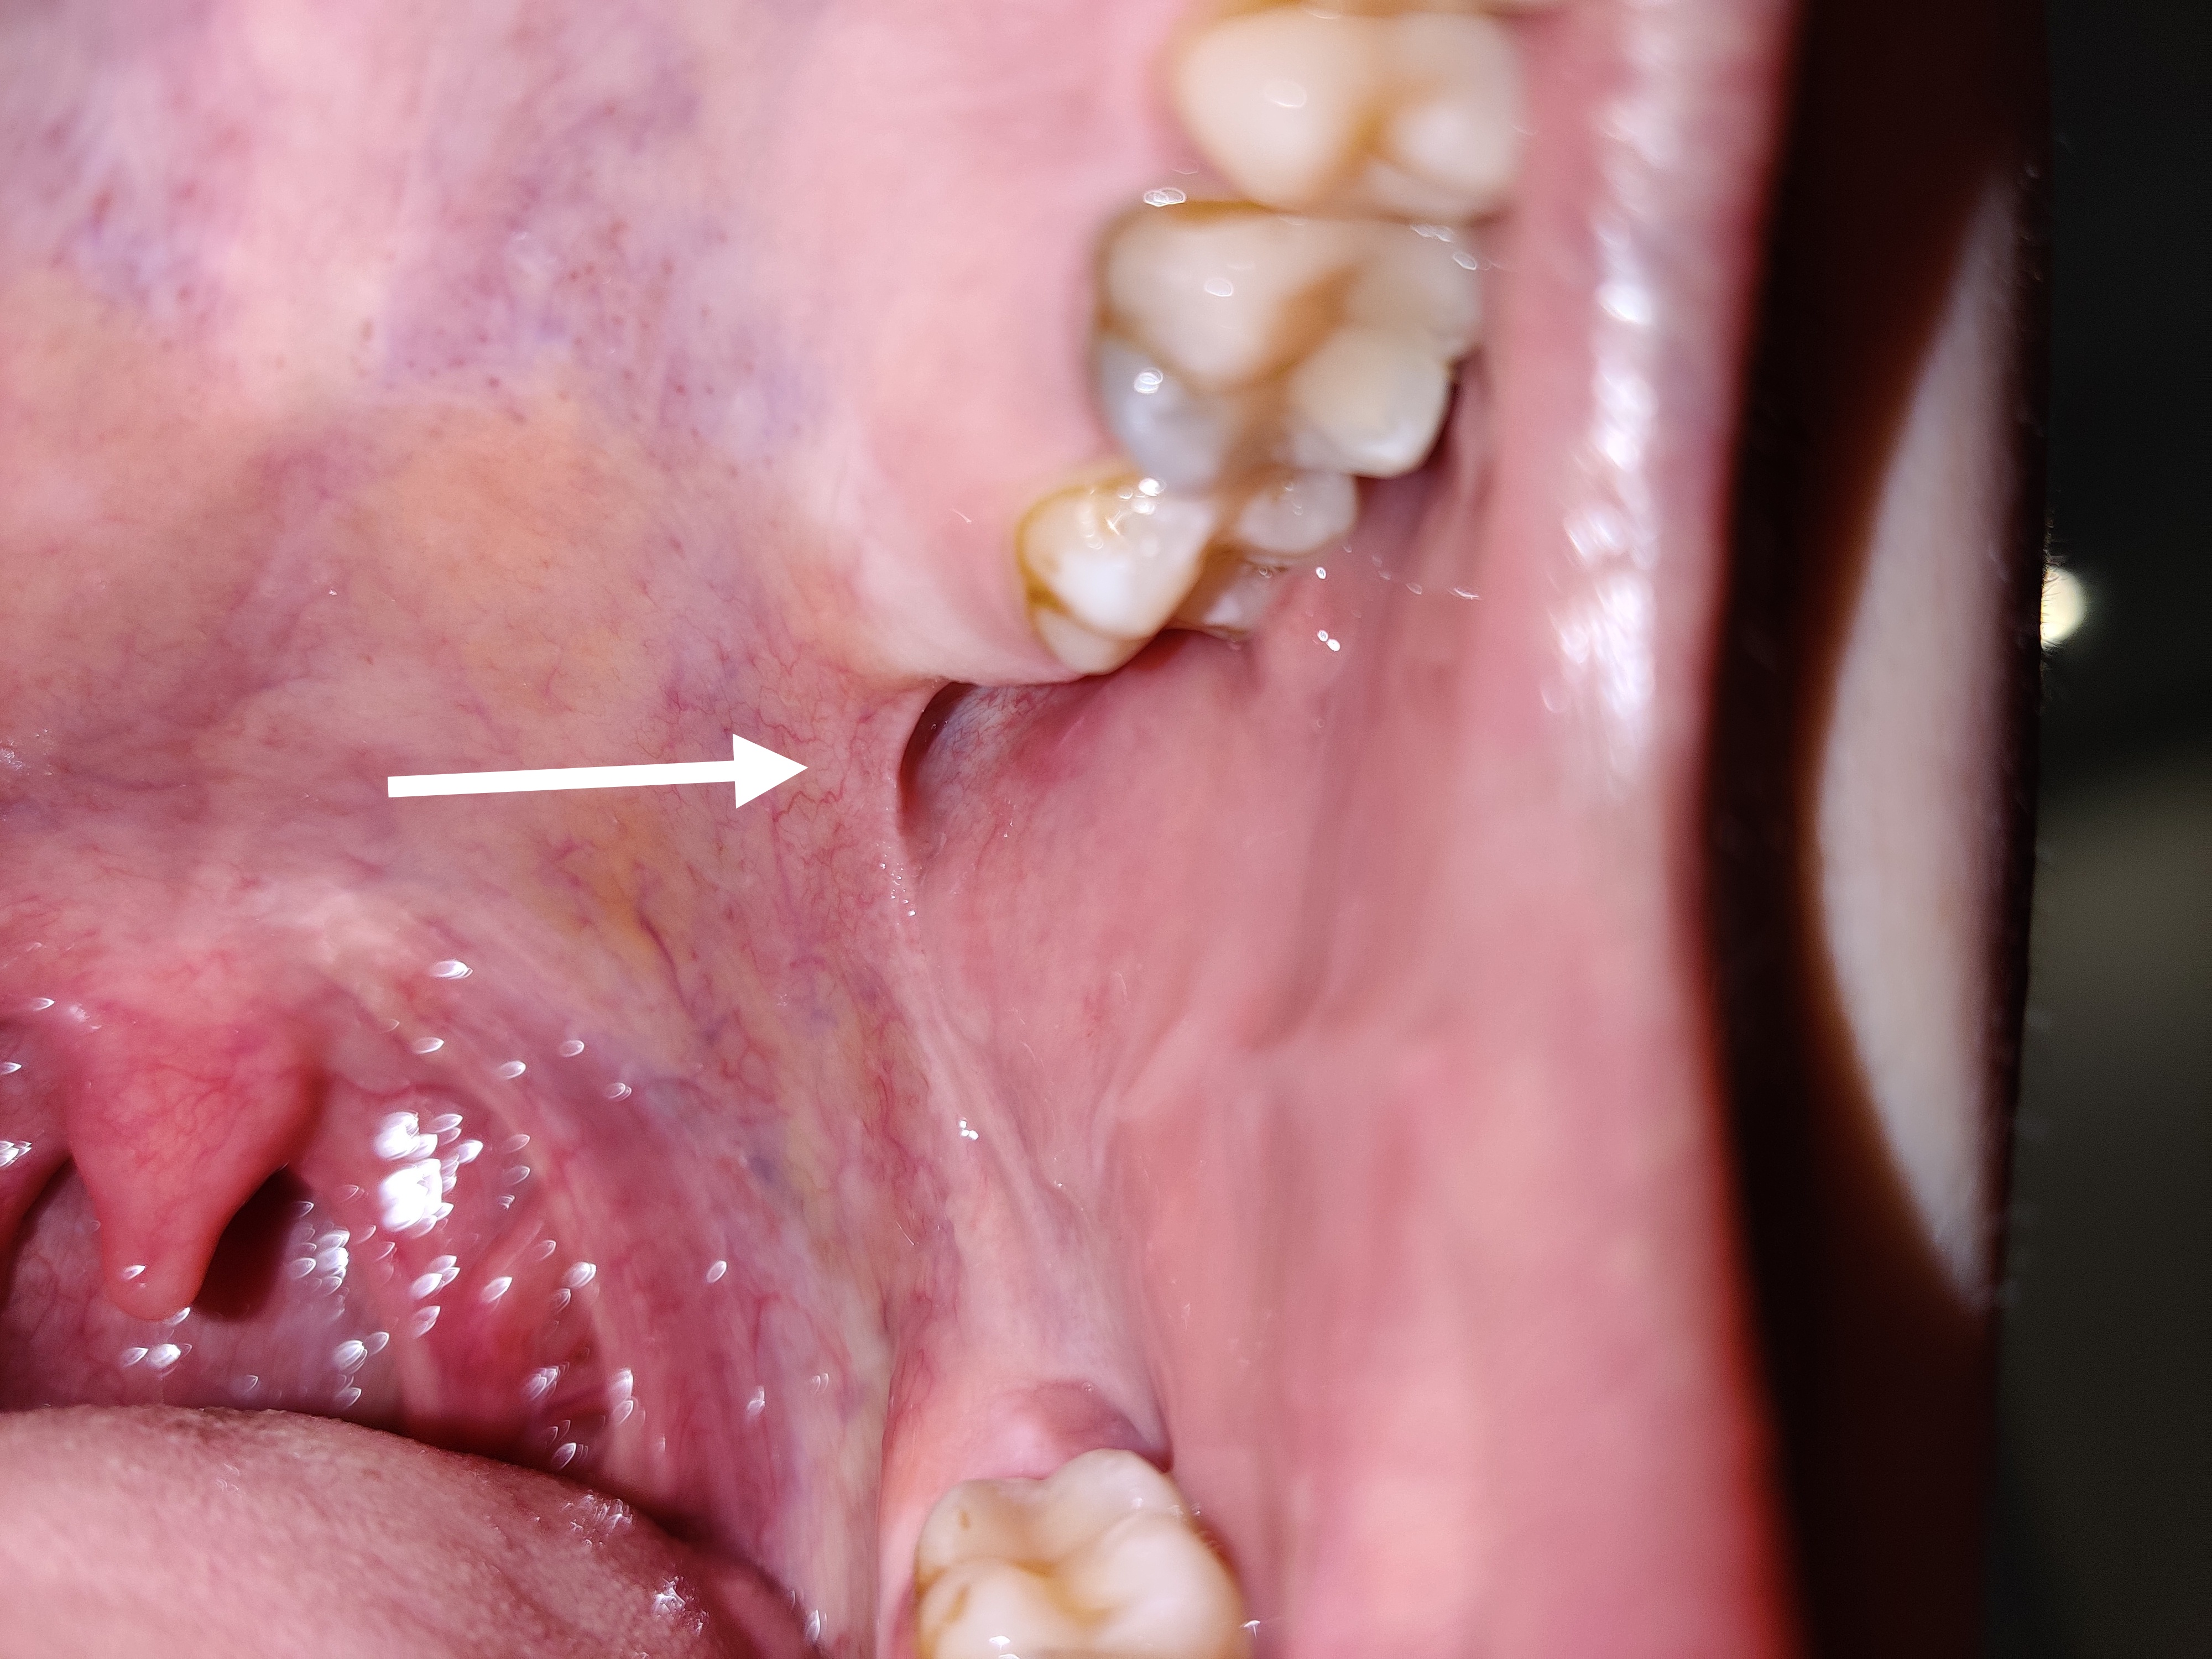

Würden sie Ihrer Einschätzung zufolge sagen, dass beide Weisheitszähne im linken Quadranten problemlos durchbrechen können oder sollten sie gezogen werden? Im Oberkiefer links habe ich des öfteren Schmerzen am Zahnfleisch, so als wäre dieses “Schleimhautbändchen” zu straff gespannt. Außerdem ist auch das Zahnfleisch darüber “weiß/heller”.